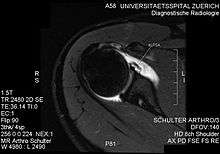

ALPSA lesion

An ALPSA (anterior labral periosteal sleeve avulsion) lesion is an injury at the front of the shoulder associated with shoulder dislocation.